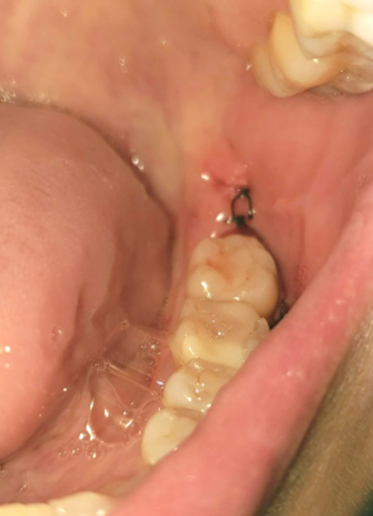

最後に、歯が抜けてぽっかり空いた空間に「スポンゼル」をいれて、

今回切開を伴いましたので、縫合して施術完了となりました。

縫合の糸は1週間後くらいに抜いてもらいました。

ゆめの森歯科では、その時に術後の経過の確認と、患部の消毒も行います💡